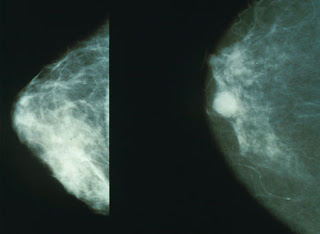

Con motivo del Día contra el cáncer de mama, se ha puesto en marcha una campaña de sensibilización e información sobre esta enfermedad.

La campaña pone de manifiesto la elevada incidencia del cáncer de mama entre la población femenina: una de cada 8 mujeres desarrollará un cáncer de mama a lo largo de su vida.

Sin embargo, la supervivencia por cáncer de mama ha mejorado notablemente en los últimos años. Las mamografías periódicas y el avance de los tratamientos permiten tasas de curación del 90%.

Un buen modelo organizativo y una atención multidisciplinar aumenta entre cinco y diez años la esperanza de vida de las mujeres con cáncer de mama, según una investigación realizada por el Hospital del Mar, que ha estudiado la evolución de más de 2.000 pacientes durante catorce años.

El estudio, que ha sido publicado en la revista Cancer Epidemiology (The International Journal of CancerEpidemiology, Detection, and Prevention) y que está basado en el registro de tumores del Hospital del Mar de Barcelona, ha demostrado que la organización de los equipos asistenciales en Unidades Funcionales es un factor clave en la supervivencia de las mujeres que padecen cáncer de mama.

El estudio concluye que las pacientes alargan su esperanza de vida si los equipos habilitados para tratar el cáncer son multidisciplinares y la persona enferma se convierte en el centro de atención de todos los profesionales que pueden intervenir.

Los índices de supervivencia pueden registrar un aumento de entre cinco y diez años si se implementan las Unidades Funcionales con los correspondientes cribados entre las mujeres en edad de riesgo.

El cáncer de mama

Unos científicos británicos han desarrollado un análisis de sangre para el diagnóstico precoz del cáncer de mama. Al parecer, este método sería más preciso que las tradicionales mamografías. Los científicos corresponden al Cancer Research UK, el Imperial College de Londres y la Universidad de Leicester, en Reino Unido.

Este nuevo método de diagnóstico de esta enfermedad sería todo un avance en la medicina, ya que, según estos científicos ayudaría a reducir tanto el estrés como la preocupación de las mujeres que se someten a una mamografía. Pero, esta metodología no solo se llevaría a cabo en el diagnóstico del cáncer de mama, la intención es que también se utilice para detectar otros tipos de tumores como el cáncer de pulmón.

La clave del novedoso test (análisis) de sangre es identificar en el ADN los marcadores que indican la presencia de cáncer de mama. Tras las primeras investigaciones realizadas, los científicos van a llevar a cabo ahora un estudio con 500 mujeres que participan en un programa de cribado de este cáncer. Una vez se tomen las muestras de sangre, se comparará el ADN de las mujeres que ya se les ha diagnosticado el cáncer con el de mujeres sanas para concluir si los marcadores que indican si una persona es víctima de esta enfermedad son o no fiables